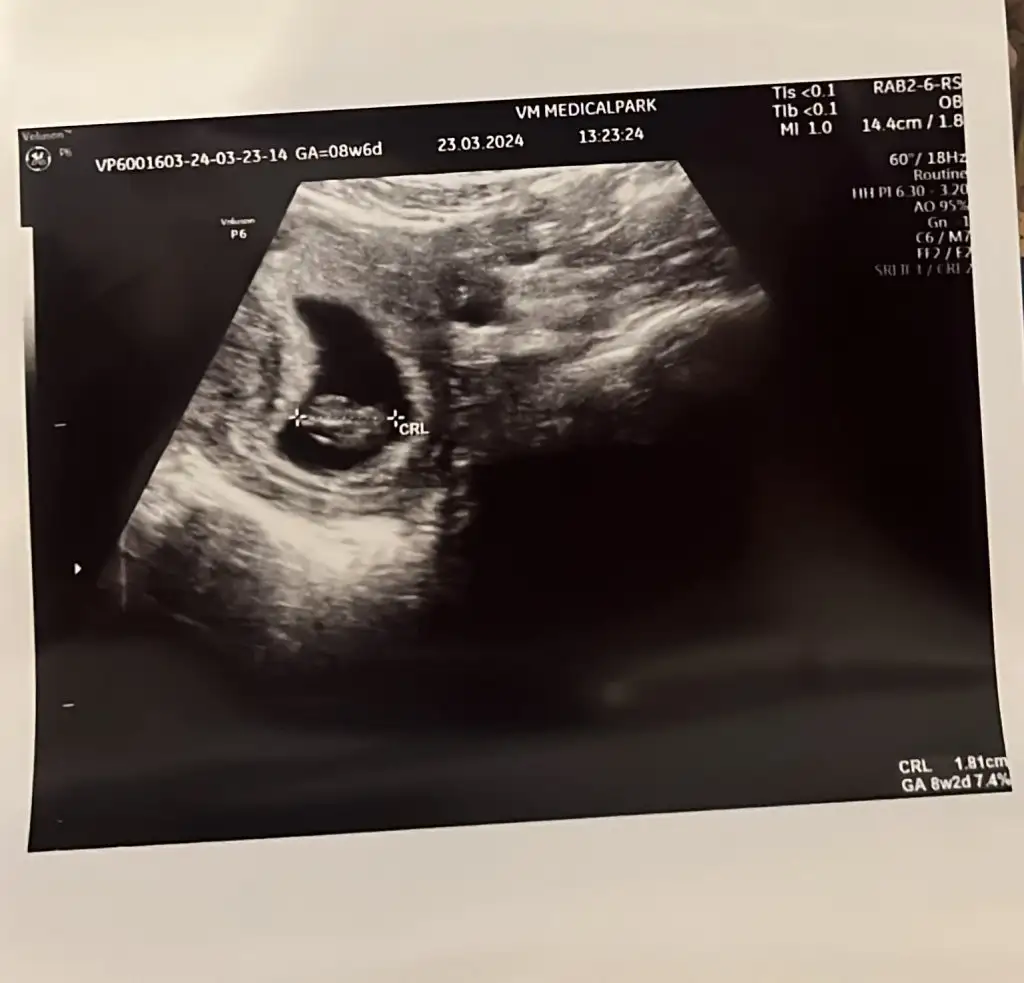

8+2. Hafta görüntüsü:

Eki Görüntüle 3406458